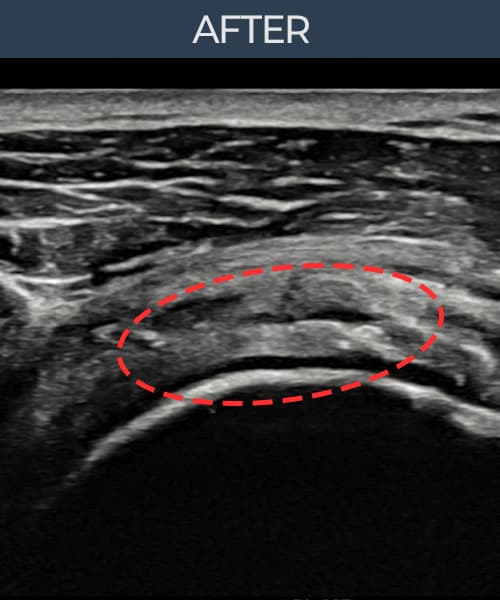

右侧 冈上肌腱 石灰化肌腱炎

10mm × 7mm